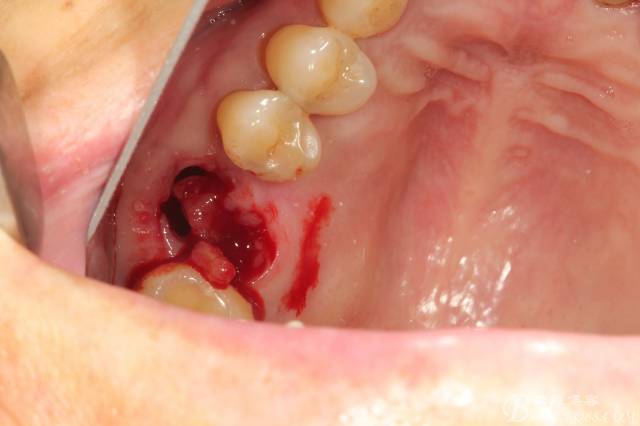

拔牙后拔牙窩里面大量肉芽組織

清理拔牙窩 清理的非常干凈包括齦緣周圍牙齦適當(dāng)修整后看到拔牙窩是巨大的,牙槽中隔已經(jīng)吸收